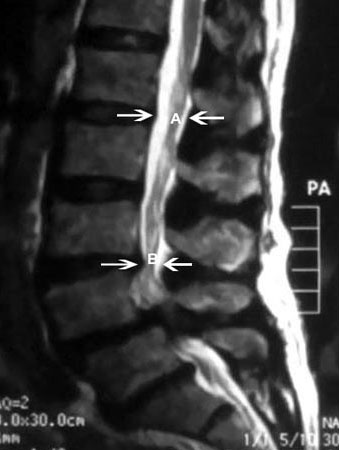

Los pacientes pueden presentar dolor de espalda que, a menudo, se describe como neurogénico, secundario a la constricción mecánica de las raíces nerviosas lumbares.[19][Figure caption and citation for the preceding image starts]: Resonancia magnética de estenosis espinal: (A) delimita el diámetro sagital normal del canal espinal. (B) delimita un estrechamiento grave del canal espinalCortesía del Dr. K. Singh; usado con autorización [Citation ends].